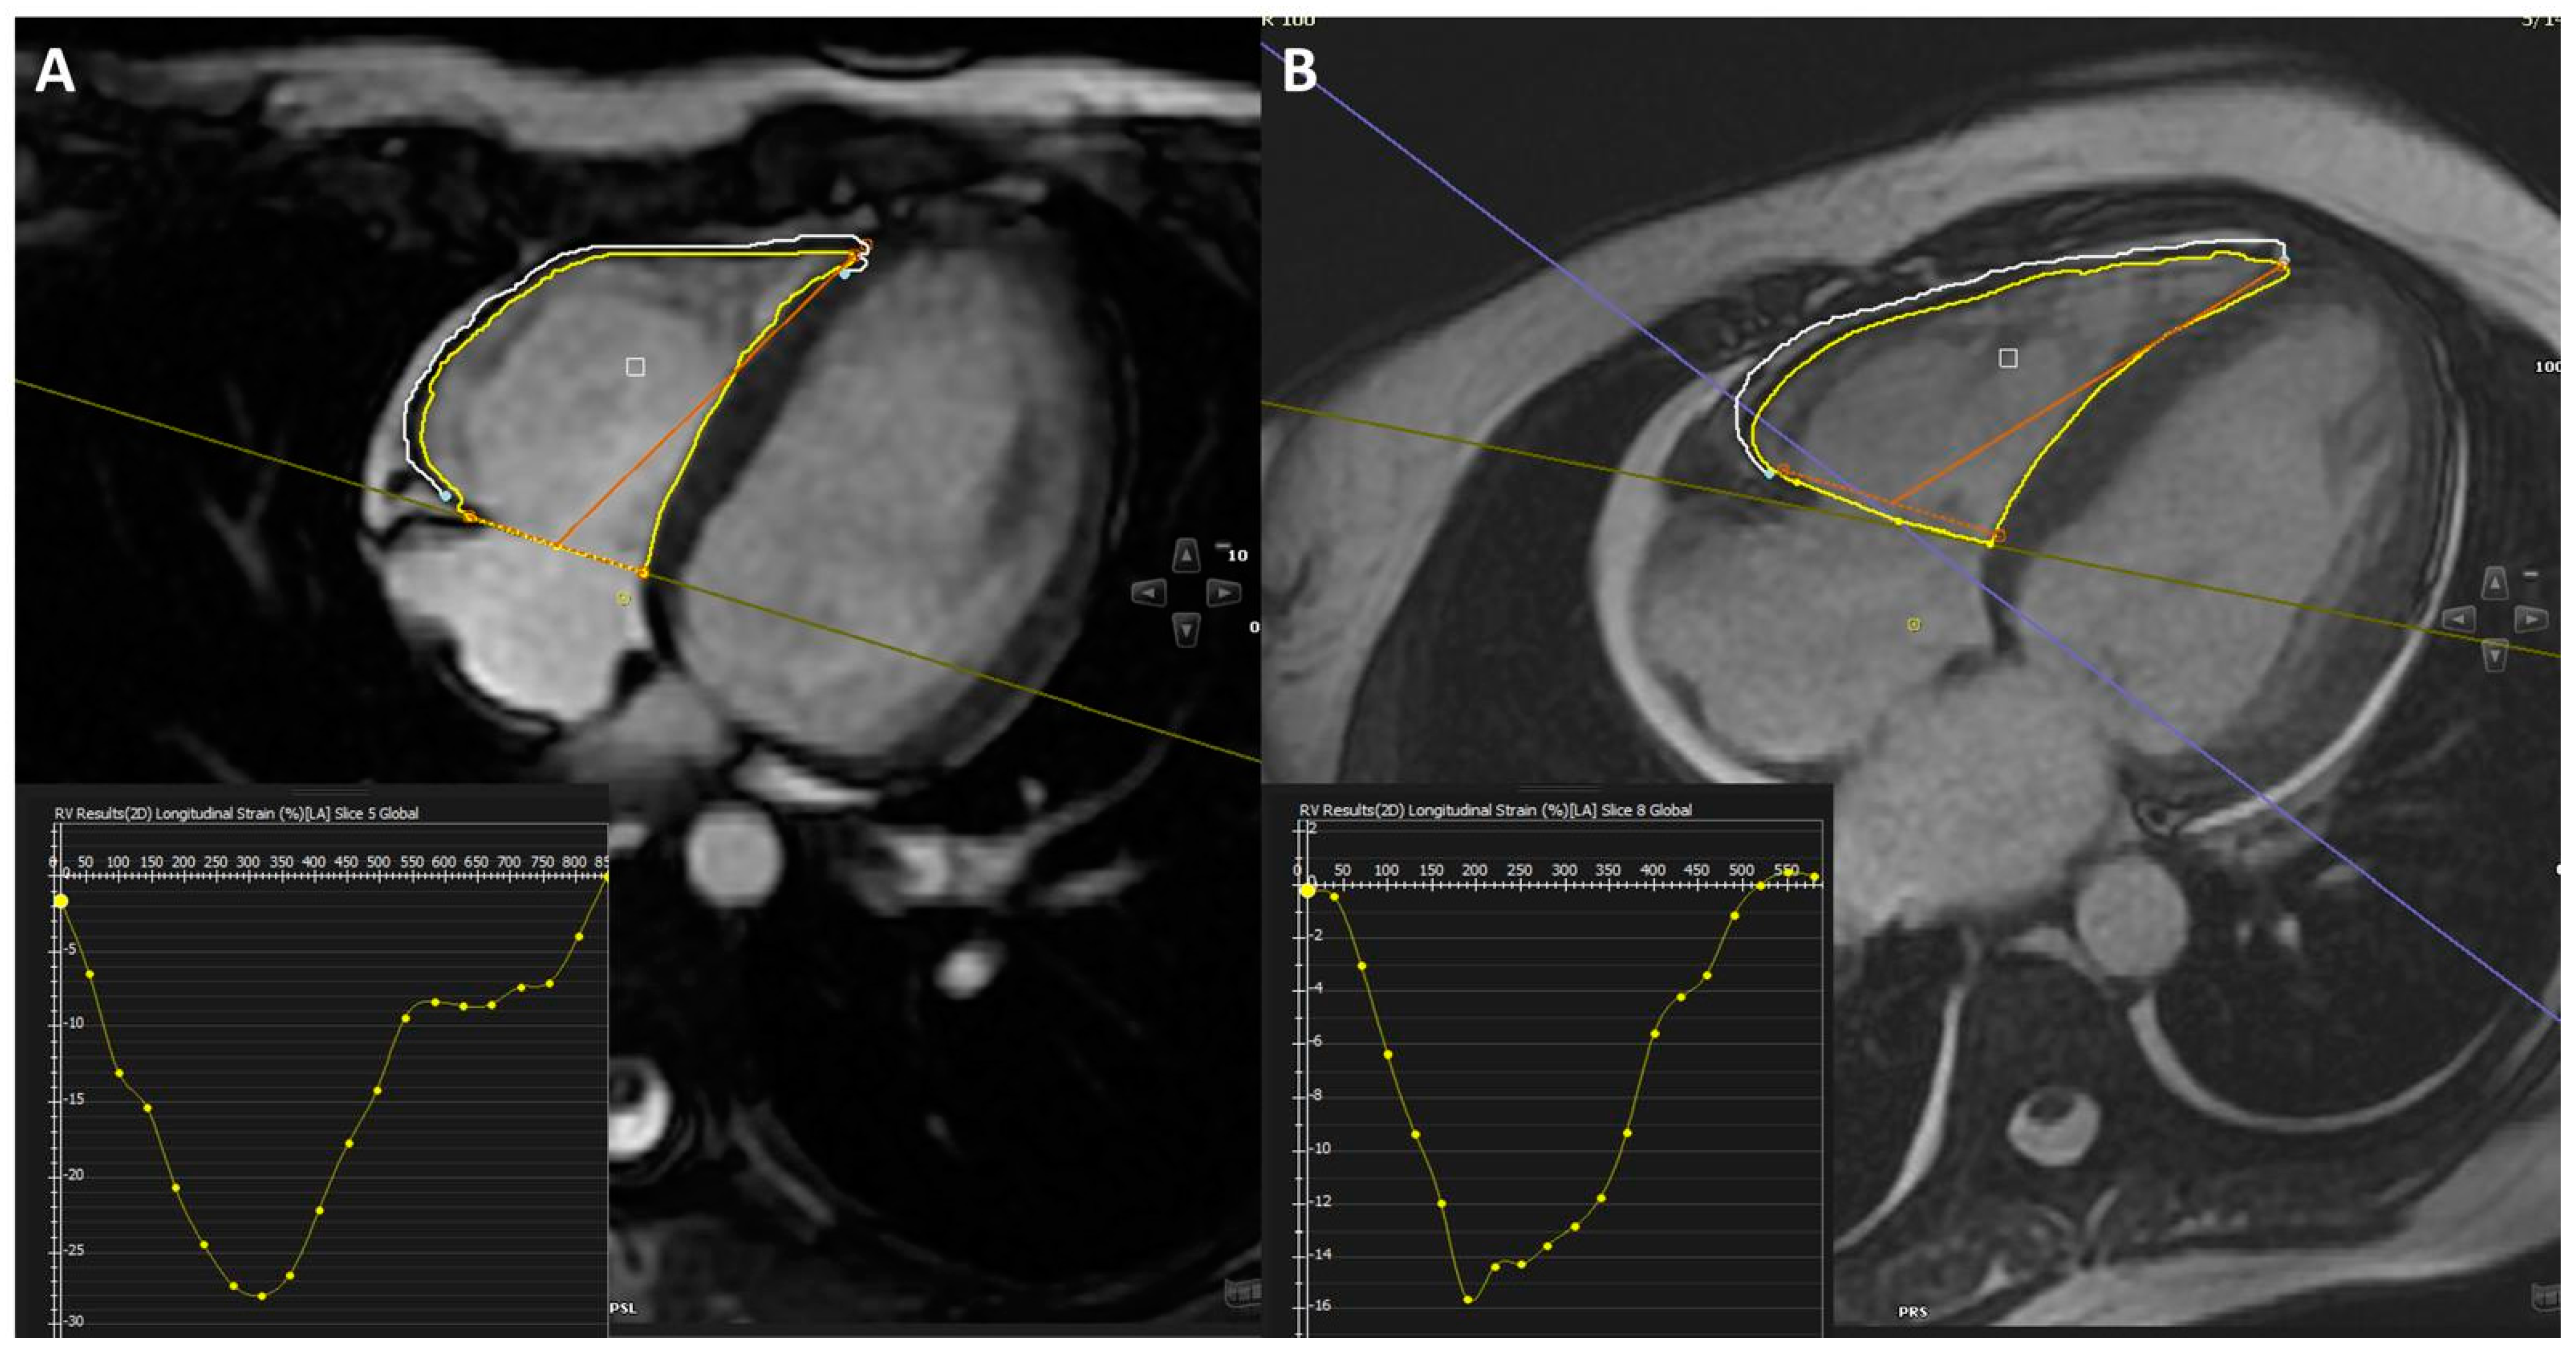

| RV strain (%) | 18.4 ± 5.4 | 21.8 ± 2.8 | 0.018 |